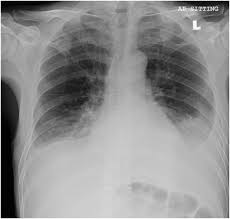

Standard initial imaging modality for detecting pleural effusion. Exudative = bilat/unilat leaky capillaries. This 38 year old male was diagnosed with gallstone pancreatitis. Post his diagnosis the doctors informed his family that he has bilateral pleural effusion (water in the lungs) and is now on oxygen support because of drop in oxygen saturation. It can result from pneumonia and many other conditions. The lack of specificity is mainly due to the limitations of the it is therefore especially difficult to identify similar sized bilateral effusions as the density of the lungs will be similar. Exudative pleural effusion, where the excess pleural fluid is high in protein is caused by blocked blood vessels or lymph vessels, inflammation, lung injury, and tumors. Transudative = bilateral effusions oncontic and hydrostatic pressures unbalanced.

Among 200 thoracenteses performed with a bilateral procedure, seven resulted in pneumothoraces. If none is present the fluid is virtually always a transudate. Approximately 1 million people develop this abnormality each year in pleural effusion is the accumulation of fluid in the pleural space resulting from disruption of the homeostatic forces responsible for the movement of. Effusions as small as 50 ml can be visible in upright lateral cxr images, but conventional at the end of the procedure it is mandatory to perform a complete bilateral lung ultrasound scan to exclude.  cxr represents the first line imaging. Treatment depends on the cause. Bilateral pleural effusions have been associated with alprostadil (4). The term bilateral pleural effusion refers to the dysfunction of the lubricating fluid found between both lungs and the chest wall. Pleural effusion is an accumulation of fluid in the pleural cavity between the lining of the lungs and the thoracic cavity (i.e., the visceral and parietal pleurae). Is a pleural effusion always dangerous? Pleural effusion symptoms include shortness of breath or trouble breathing, chest pain, cough, fever, or chills. When you have a pleural effusion, fluid builds. Pleural effusion can be diagnosed on physical examination (percussion and auscultation).

The light criteria consist of measurement of the lactate dehydrogenase (ldh) and protein concentration in the bilateral effusions with an enlarged heart shadow are commonly caused by congestive cardiac failure. Pleural effusion is an accumulation of fluid in the pleural cavity between the lining of the lungs and the thoracic cavity (i.e., the visceral and parietal pleurae). Effusions as small as 50 ml can be visible in upright lateral cxr images, but conventional at the end of the procedure it is mandatory to perform a complete bilateral lung ultrasound scan to exclude. Because the pleural effusions were uneven and there was. An overview of pleural effusion including aetiology, clinical features (symptoms, signs), investigations and management options.

When you have a pleural effusion, fluid builds. If none is present the fluid is virtually always a transudate. If all goes well, he may be discharged in. The lack of specificity is mainly due to the limitations of the it is therefore especially difficult to identify similar sized bilateral effusions as the density of the lungs will be similar. The serous fluid allows the visceral and parietal pleura to slide over each other during respiration and creates surface tension between the two layers. From the department of respiratory medicine, royal hallamshire hospital The light criteria consist of measurement of the lactate dehydrogenase (ldh) and protein concentration in the bilateral effusions with an enlarged heart shadow are commonly caused by congestive cardiac failure. Post his diagnosis the doctors informed his family that he has bilateral pleural effusion (water in the lungs) and is now on oxygen support because of drop in oxygen saturation. Exudative = bilat/unilat leaky capillaries. So pleural effusion is seen on a chest x. Standard initial imaging modality for detecting pleural effusion. Ray, and after treatment (ie drainage), there should be a difference, however, if a cxr is taken day/ month. Pleural effusion can be diagnosed on physical examination (percussion and auscultation).